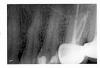

DokDent Опубликовано 17 октября, 2010 Поделиться Опубликовано 17 октября, 2010 Добрый день, уважаемые стоматологи и иже с ними. Больше месяца ноет слева верхний шестой зуб под коронкой (каналы пролечены, стоит штифт и мост с седьмым зубом). С момента ноющей боли - насморк. Была у стоматолога - сделал снимок, говорит, что ничего не видит. Была у лора, сделали снимок, слева ничего не нашли, справа был гайморит, который пролечили антибиотиками. Гайморит прошел, насморк в левой ноздре (где ноет зуб) остался. Вдобавок добавилась боль в левой верхней челюсти, в районе уха. Особенно тяжко по ночам - ощущение жжения и ноющего зуба. У меня 2 вопроса:1. что со мной, доктор?2. к какому врачу обратиться, чтобы избавиться от боли?Снимок прилагаю. По данному снимку пульпитная боль может исходить из 5-го зуба.Неплохо бы посмотреть 7-й. Ссылка на комментарий

adelanta Опубликовано 17 октября, 2010 Автор Поделиться Опубликовано 17 октября, 2010 По данному снимку пульпитная боль может исходить из 5-го зуба.Неплохо бы посмотреть 7-й. Спасибо! А может быть насморк и боль в челюсти реакцией на зубную боль? Панорамный снимок вот http://forum.stom.ru/index.php?act=Attach&type=post&id=4033 снимок некачественный-зона повышенного интереса обрезана и осталась за кадром. Хм, чего дали на руки, то и оправила вам. такие снимки делают в ведомственной поликлинике г. москвы... (ничего не обрезала, честно!!!) а за размещение снимка простите, я не со зла, а по незнанию... Ссылка на комментарий

Большой Зеленый Опубликовано 17 октября, 2010 Поделиться Опубликовано 17 октября, 2010 на панорамном снимке до лечения и коронок - левосторонний гайморит.+1 тоже вижу гайморит слева Ссылка на комментарий

DokDent Опубликовано 18 октября, 2010 Поделиться Опубликовано 18 октября, 2010 Боль периодическая, возникающая только к вечеру и ночью. Кашля нет, усиление симптомов при опускании головы есть, если выхожу на улицу, начинает несильно болеть челюсть, да. Аллергией страдаю только на клубнику (отек квинке), но ее не ем. Облегчения не наступило потому что, как сегодня объяснил доктор, у меня "остаточное явление" гайморита и его надо долечивать. Стоматолог велел сделать ЭОД. Лицевой хирург также отправил лечить нос, порекомендовав во время воспаления привязывать на ночь челюсть платочком.... Обоснуйте, пожалуйста, ваши смущения? Пульпит на 5 зубе?Настораживает периодичность появления боли(усиливается ночью и при смене температурного режима)-это может указывать на воспаление нерва.(хотя и не обязательно)+пломба прилежит близко к полости зуба(хотя это может быть и такая проекция).ночной кашель и усиление симптомов при опускании головы характерны для гайморита.Про аллергию спросила потому,что гайморит может быть и аллергического х-ра,а он лечится по-другому.Абсолютно согласна с нашими и Вашими докторами насчёт гайморита,но просто думаю:нет ли наслоения пульпита?Диагностика-дело сложное,здесь важна каждая мелочь Ссылка на комментарий